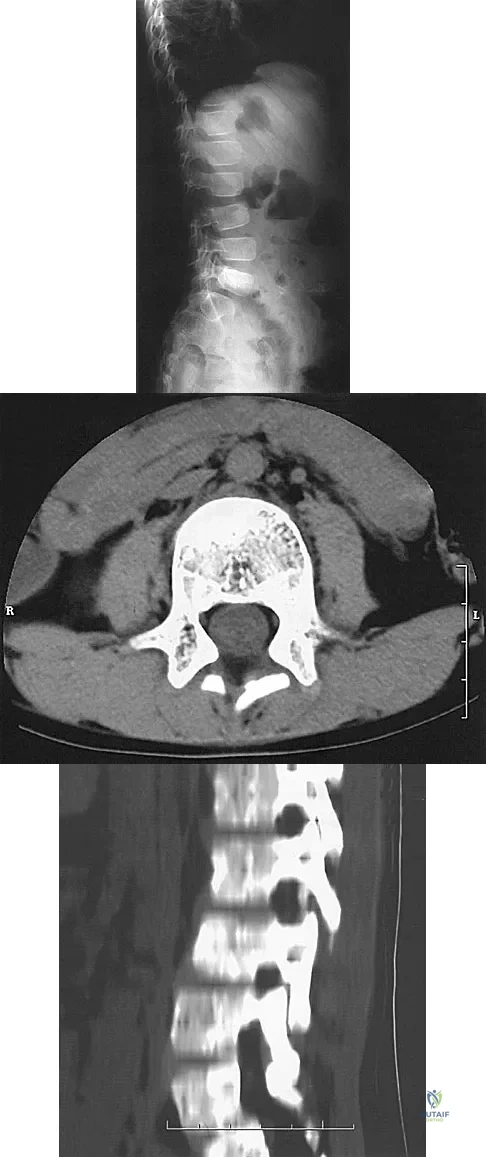

Figure 12 shows the lumbar CT scan of a 24-year-old man who was injured in a snowmobile accident. What is the mechanism of injury?

Explanation